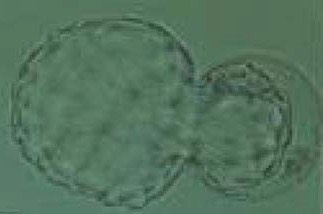

648. По системе оценки качества бластоцист, предложенной гарднером, эмбрион оценивается как